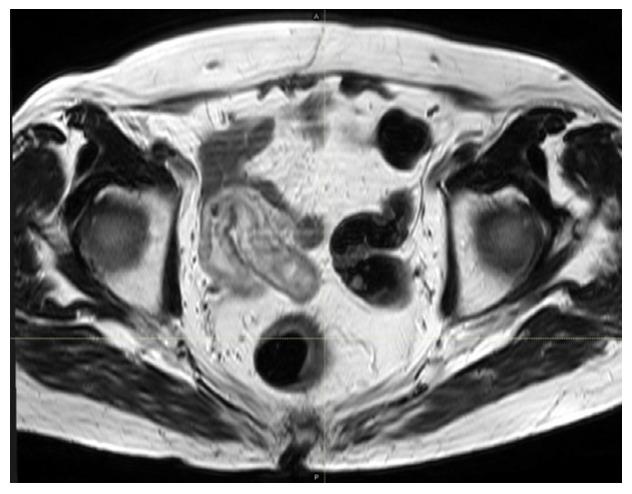

Capecitabine-Induced Ileitis during Neoadjuvant Pelvic Radio-Chemotherapy for Locally Advanced Rectal Cancer: A Case Report with Literature Review.

We report on a clinical case of capecitabine-induced acute ileitis in a patient treated with pre-operative concurrent chemoradiation with capecitabine for locally advanced rectal cancer and provide a comprehensive literature review. This a rare, but life-threatening, clinical situation, that clinicians should be aware of. Severe persistent diarrhea is the most frequent clinical feature and computed tomography is a valid tool for diagnosis. Conservative management includes capecitabine withdrawal, antidiarrheal therapy and endovenous hydration, together with dietary modifications and broad-spectrum antibiotics. Pelvic irradiation represents an adjunctive risk factor, which may increase the likelihood of occurrence of terminal ileitis. Early recognition and prompt intervention are crucial for successful clinical management.